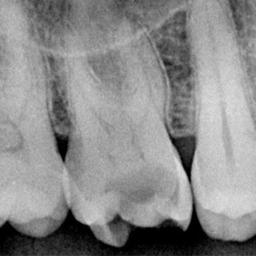

정밀 진단

3D CT X-RAY를 통한 정확한 충치 진단